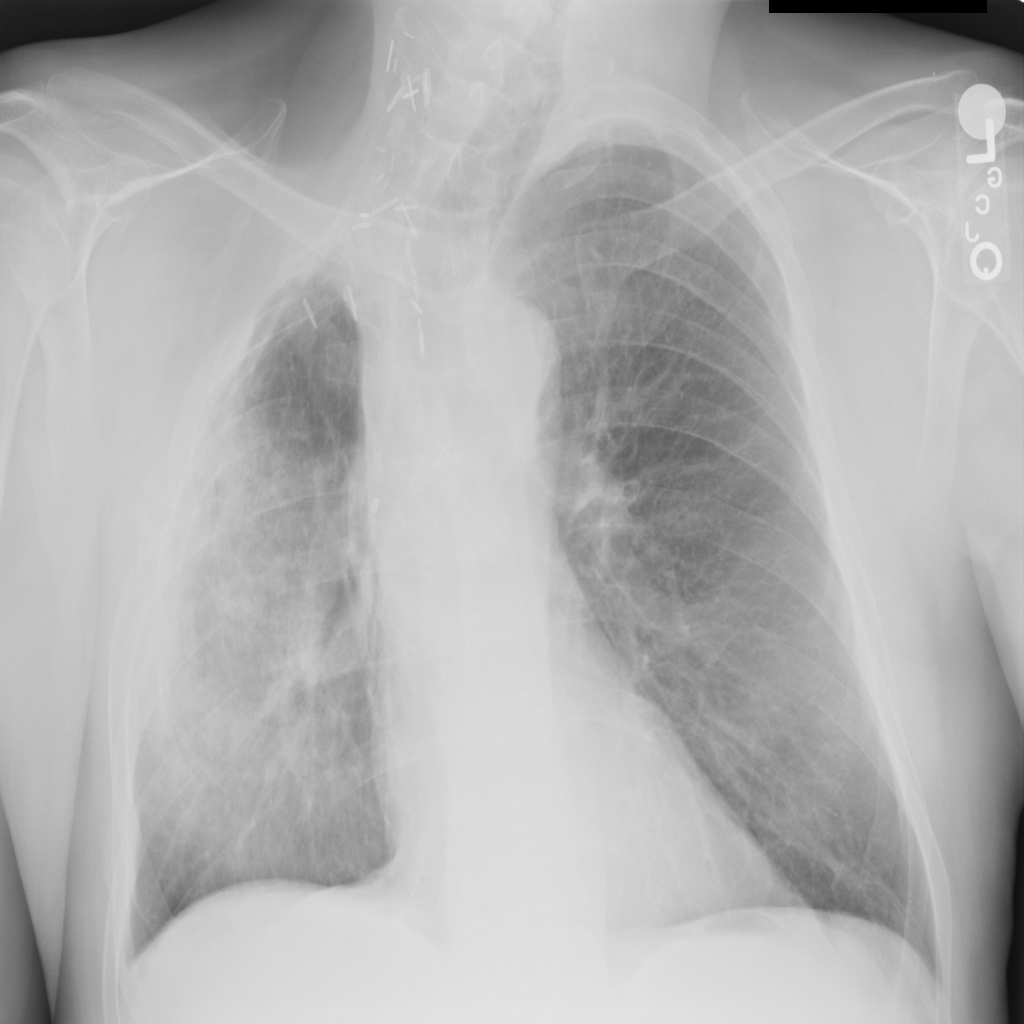

PAT-C255 · IMG-000Emphysema

PAT-C255 · IMG-000

PA